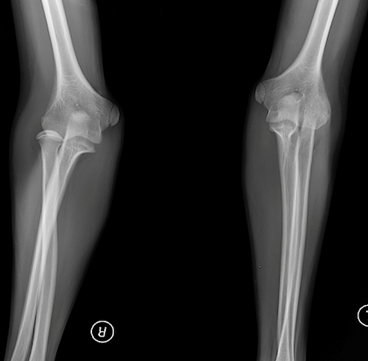

Запитання 21

РОЗПІЗНАЙТЕ НА РЕНТГЕНОГРАМІ СУГЛОБ, ЩО СКЛАДАЄТЬСЯ З ТРЬОХ СУГЛОБІВ, ЯКІ МАЮТЬ СПІЛЬНУ КАПСУЛУ.

варіанти відповідей

Запитання 26

НА ЯКІЙ РЕНТГЕНОГРАМІ Є КІСТКИ, ЩО НЕ НАЛЕЖАТЬ ДО СКЕЛЕТУ НИЖНЬОЇ КІНЦІВКИ?